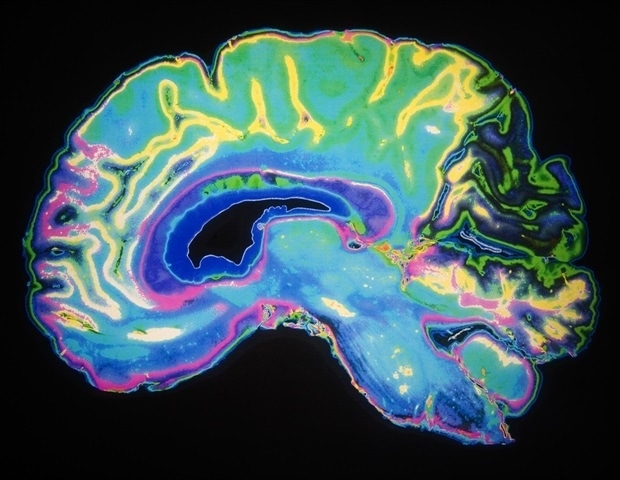

Αυτές οι λειτουργίες σχετίζονται με τις περιοχές του εγκεφάλου όπου οι αργά αναπτυσσόμενοι γλοιώματα εμφανίζονται πιο συχνά: στον μετωπιαίο λοβό, ο οποίος διαχειρίζεται τη συμπεριφορά, την προσωπικότητα, την κρίση και τον έλεγχο των παρορμήσεων, και στον κροταφικό λοβό, ο οποίος ελέγχει την ακοή, τη μνήμη, τη γλώσσα και τα συναισθήματα.